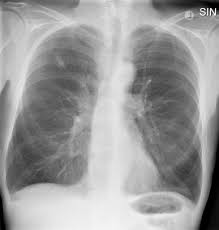

Can Lung Cancer Be Mistaken For Tuberculosis / Cancer And Tb / Since mycobacterium tuberculosis (mtb) is an intracellular organism, bacterial dna could integrate to bronchial epithelial cells inducing neoplastic transformation.. Primary tuberculosis usually begins in childhood and affects the lungs and bronchial lymphatic glands of the lung roots. Tuberculosis (tb) is a contagious infection that usually attacks your lungs. The occurrence of pulmonary tuberculosis (ptb) and lung cancer as comorbidities has been extensively discussed in many studies. Most lung cancers do not cause any symptoms until they have spread, but some people with early lung cancer do have symptoms. Pulmonary tuberculosis is caused by mycobacterium tuberculosis, which produces characteristic tuberculosis changes in the lung.

Tuberculosis, a disease that used to be common in the uk and other western countries, was thought to have been successfully controlled when vaccination was introduced. Interestingly so, tuberculosis has been known to mimic lung cancer due to its presentation in the form of pulmonary infiltrates and mediastinal lymphadenopathy however, in the reported cases where pulmonary tuberculosis was mistaken for pulmonary malignancy, a number of different, costly. Iteither enlargesas disease progresses or, much. Lung can suggest early symptom of tuberculosis). You can't get it from shaking hands with someone who has it or by sharing their food or drink.

Urogenital Tuberculosis Epidemiology Pathogenesis And Clinical Features Nature Reviews Urology from media.springernature.com You can get tb by breathing in air droplets from a cough or sneeze of an infected person. Lung can suggest early symptom of tuberculosis). Lung cancer is most often discovered by mistake if it is detected in the early stages. When people with lung tb cough, sneeze or spit, they propel the tb germs into the air. Tuberculosis (tb) is a contagious infection that usually attacks your lungs. Tb is spread from person to person through the air. 90% of cases being attributable to smoking. Patients with lung cancer are often misdiagnosed as pulmonary tuberculosis leading to delay in the correct diagnosis as well as exposure to inappropriate.